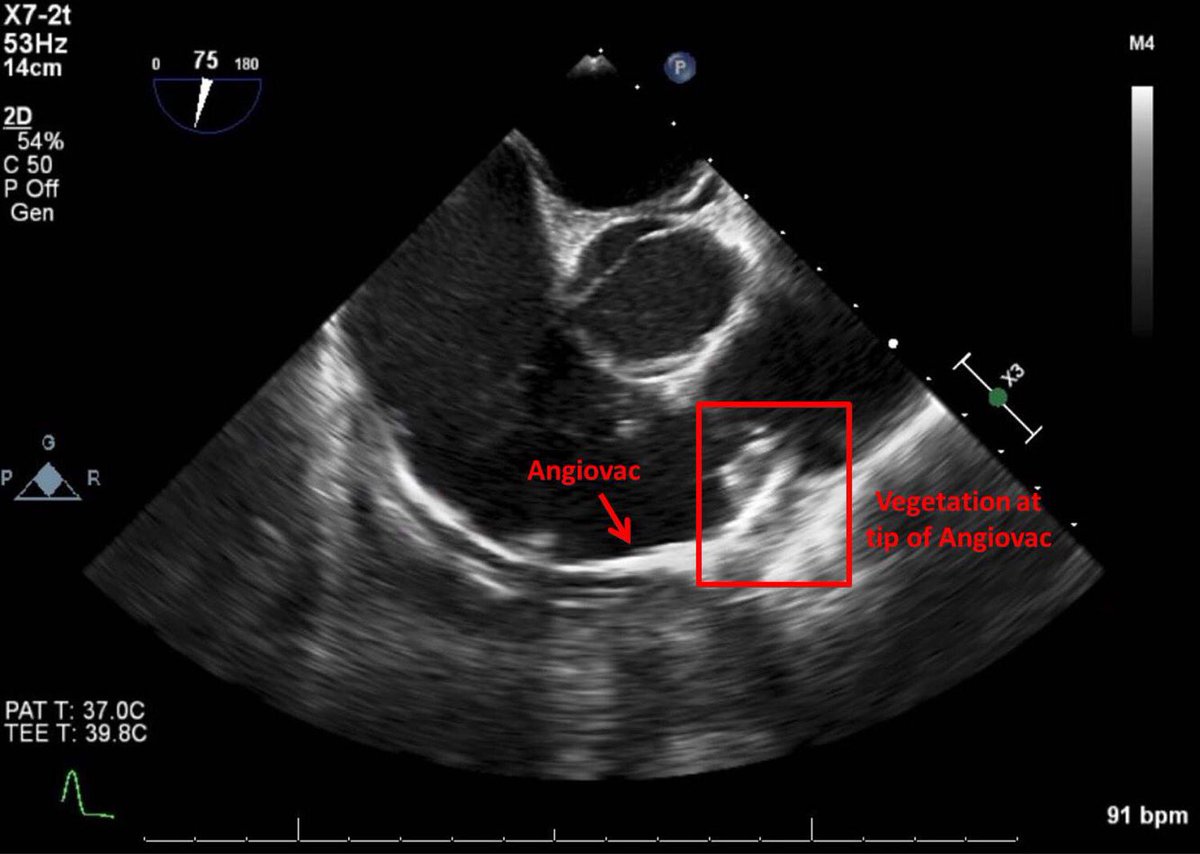

Part 2/2: 25 yo M IVDA with pulmonic valve vegetation. Successful Angiovac aspiration of 1.1cm vegetation with TEE guidance and no contrast. Vegetation positive for micrococcus luteus, antibiotics adjusted accordingly. @Striker9DO @gsiskin @SIRRFS #withoutascalpel #IRad